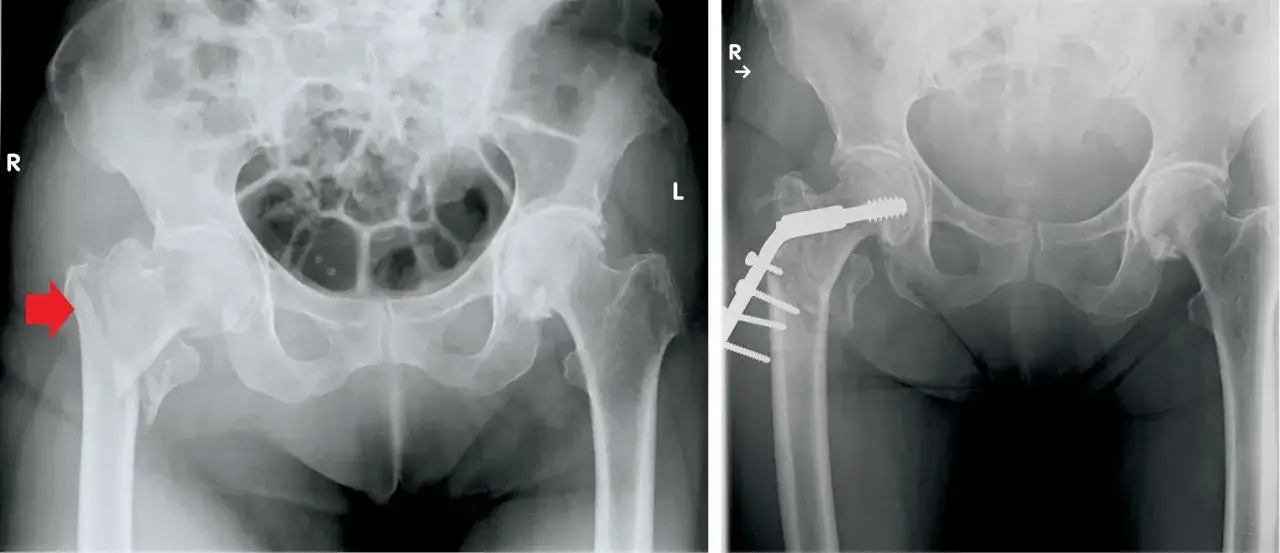

Rodzaj złamania

Złamanie kości udowej może dotyczyć różnych jej części, co wpływa na czas zrastania. Złamania trzonu kości udowej zazwyczaj goją się szybciej niż złamania szyjki. Wynika to z lepszego ukrwienia trzonu kości. Złamanie szyjki kości udowej często wymaga dłuższego okresu rekonwalescencji, szczególnie u osób starszych, ze względu na gorsze ukrwienie tej okolicy.

Metoda leczenia

Leczenie złamania kości udowej może być operacyjne lub zachowawcze, co wpływa na czas gojenia. Operacja, polegająca na stabilizacji złamania za pomocą implantów, często przyspiesza proces gojenia. Leczenie zachowawcze, stosowane rzadziej, może wydłużyć czas powrotu do sprawności, ale jest konieczne w niektórych przypadkach.